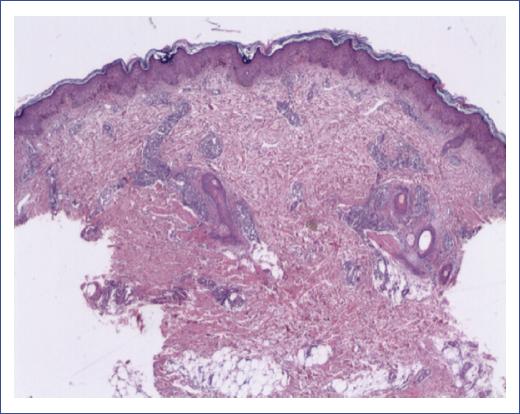

Figure 4 Perivascular, periannexal, and interstitial infiltrate consisting of atypical cells (hematoxylin and eosin staining).